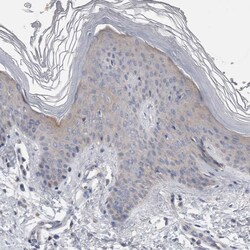

| Applications | Immunohistochemistry (Paraffin), Western Blot |